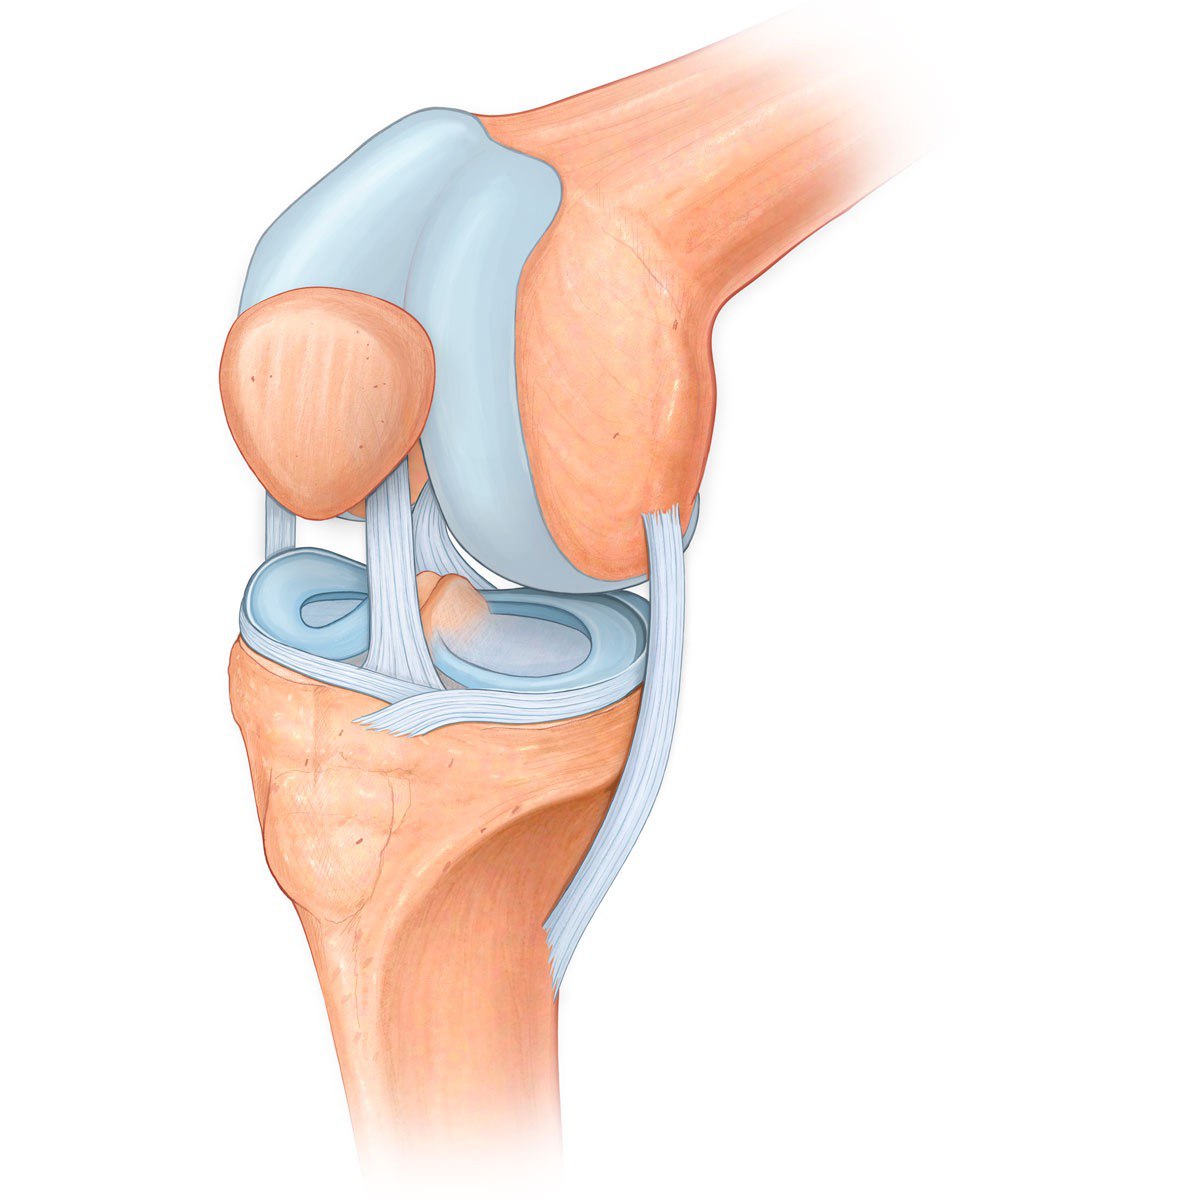

Рисунки Суставов: Анатомические Иллюстрации